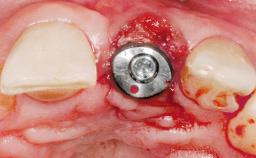

A 33-year-old female patient presented with an upper left central incisor that required extraction after a failed endodontic therapy. The tooth had been traumatized when the patient was a teenager and had undergone several endodontic treatments, including two apicectomy procedures. The patient was in good health and did not smoke. Clinical examination showed that the patient had a high lip line. In full smile, the gingival margins of the upper teeth were visible to the first molars. The gingival margins of central incisors 11 and 21 were only just showing. Examination of tooth 21 confirmed that the tooth was mobile and had hypererupted by 1 mm.